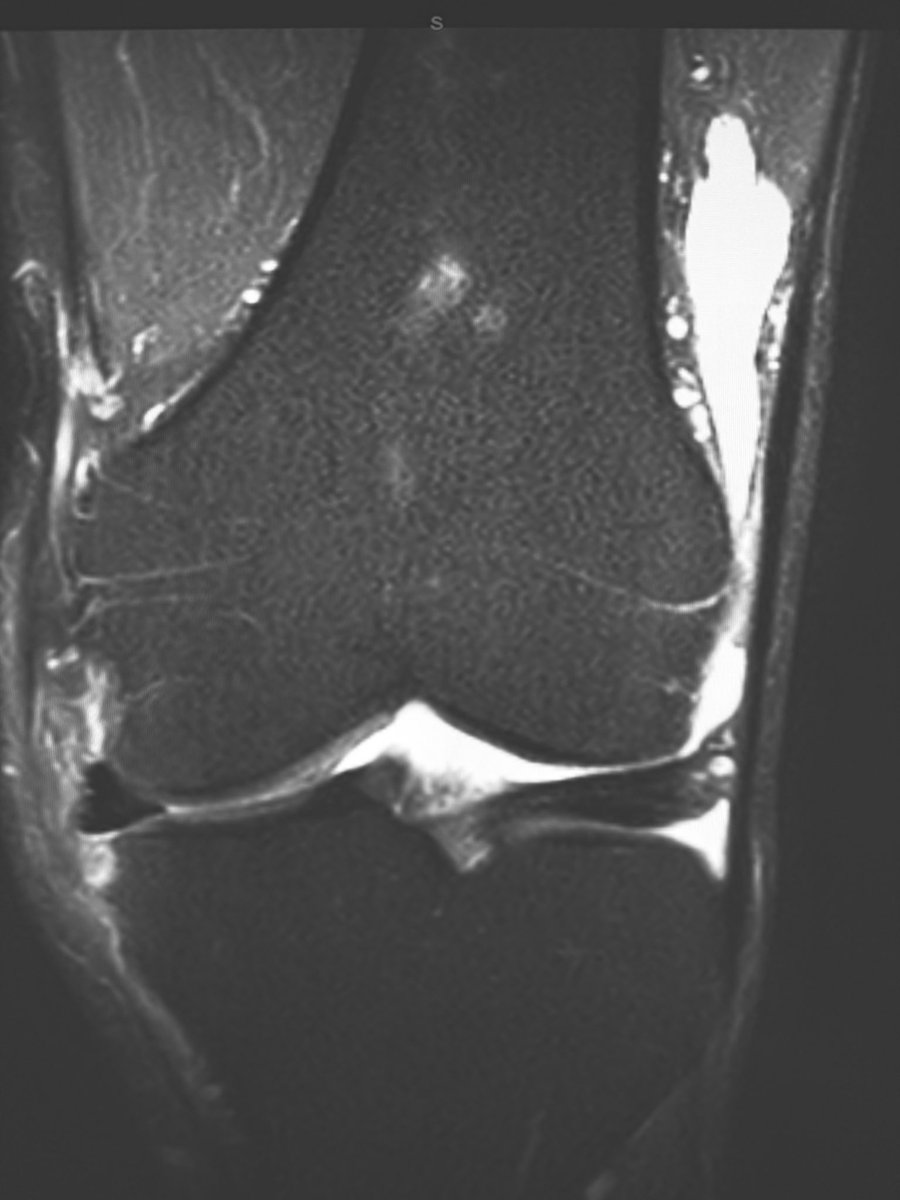

Before attributing ‘joint space narrowing’ at the knee to arthritis, take a look at the meniscus (yes, you can faintly see menisci on radiographs) - often the narrowing is due to meniscal extrusion, which in turn is related to meniscal tear.